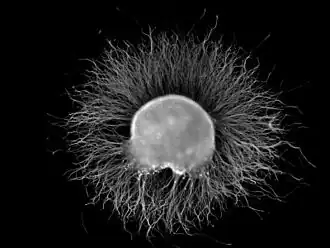

Ganglia are primarily made up of somata and dendritic structures, which are bundled or connected. Ganglia often interconnect with other ganglia to form a complex system of ganglia known as a plexus. Ganglia provide relay points and intermediary connections between different neurological structures in the body, such as the peripheral and central nervous systems.